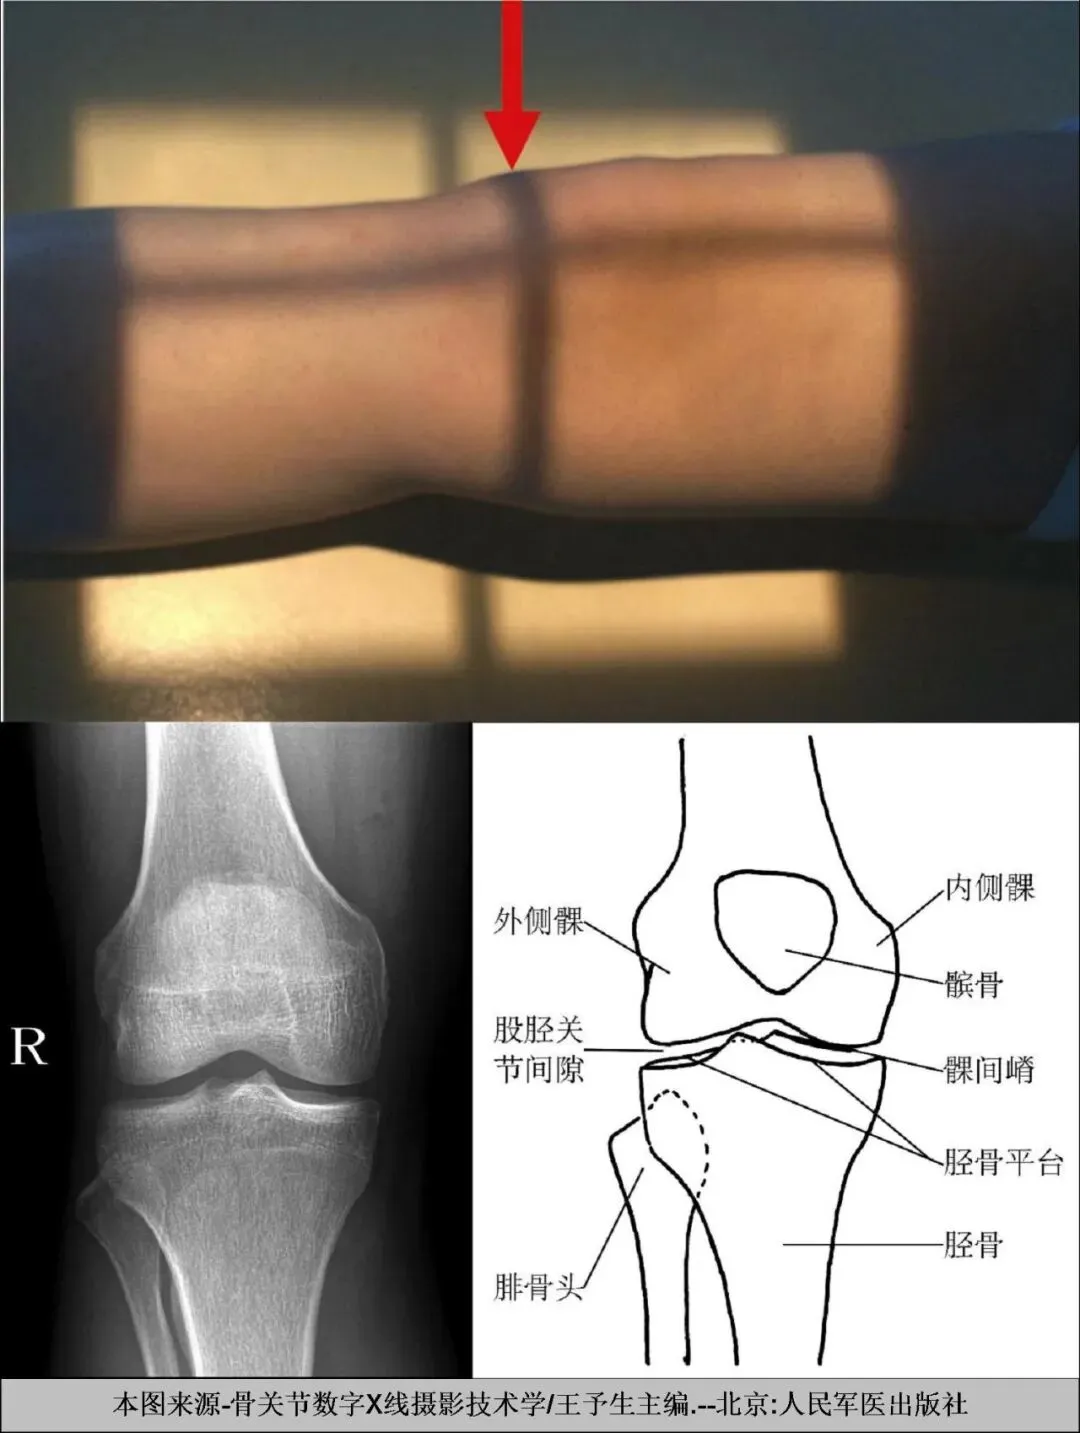

A、膝关节正位X线摄影要点:

一.体位设计:

1. 患者仰卧或坐于摄影台上,被检侧下肢伸直,足尖向上稍内旋。

2.将髌骨下缘置于探测器中心,小腿长轴与探测器长轴平行。

3.探测器上缘包括股骨下段,下缘包括胫腓骨上段。

二.中心线

对准髌骨下缘,垂直射入探测器中心。

四.图像质控

1. 图像包括股骨两髁、胫骨平台及腓骨头,髌骨位于内外髁正中。

2.关节面位于图像正中。

3. 腓骨头与胫骨重叠约1/3。

4.膝关节诸骨纹理清晰可见,周围软组织层次可见。